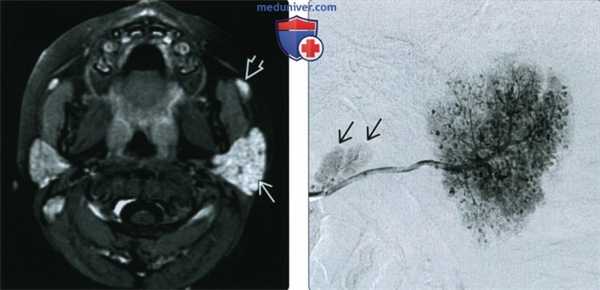

(Слева) МРТ Т1ВИ FS c КУ, аксиальная проекция. Ребенок с рецидивирующим паротитом. Левая железа увеличена в размерах и интенсивно накапливает контрастное вещество. Значительного воспаления жировой клетчатки нет. Обратите внимание, что в добавочной железистой ткани также происходит умеренное накопление контраста.

(Справа) Сиалограмма в боковой проекции, этот же пациент. В левой железе определяются множественные небольшие капли/скопления контраста, также они имеются и в добавочной железе. Обратите внимание, что размер протоков остается нормальным.

3. МРТ при остром паротите:

• Т2ВИ:

о Диффузный гиперинтенсивный сигнал ± локальные участки сигнала повышенной интенсивности (микроабсцессы или расширение протоков)

• Т1ВИ с КУ:

о Увеличенная околоушная железа, равномерно неинтенсивно накапливающая контрастное вещество

о Абсцесс: скопление жидкости с периферическим кольцом накопления контраста